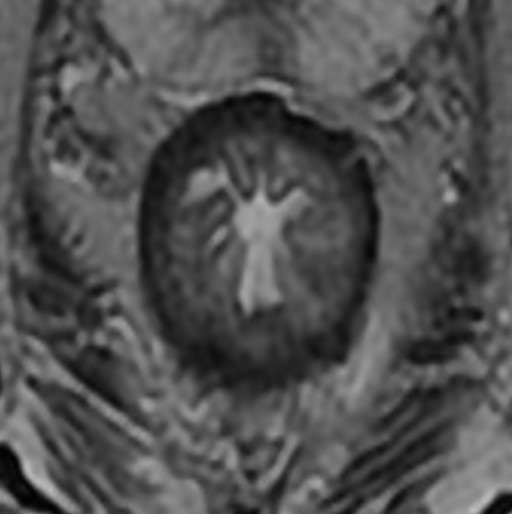

В нижних отделах прямая кишка окружена мышцами тазового дна, включая мышцу levator ani и ее составляющие: mm. puborectalis, pubococcygeus, iliococcygeus [9] (рис. 2). Мышца puborectalis формирует мышечную петлю вокруг прямой кишки на уровне аноректального соединения, создавая аноректальный угол, который играет важную роль в механизме удержания кала [9]. При МРТ в аксиальной плоскости мышца puborectalis визуализируется как U-образная гипоинтенсивная структура, охватывающая прямую кишку [6].